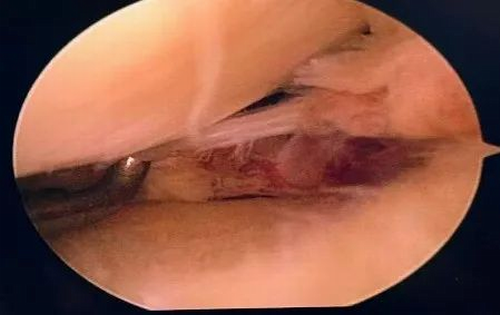

患者,汪某,因“膝关节疼痛”前往奉节县中医院就诊,磁共振检查提示“左膝关节内侧半月板后根撕裂‘’,完善术前准备,与患者详细沟通治疗方案后,于2月10日在全麻下行关节镜手术,术中发现左膝内侧半月板后根部撕裂,术中给予后根部止点重建,术后探查半月板根部稳定,手术非常顺利,患者十分满意,已康复出院。

镜下可见后根部撕裂